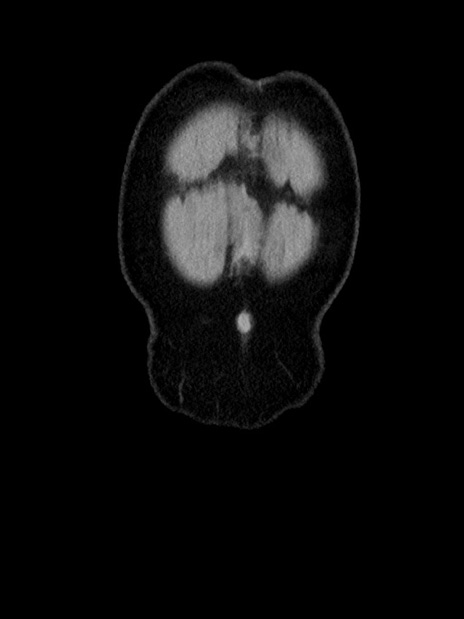

症例35(冠状断像)

横断像